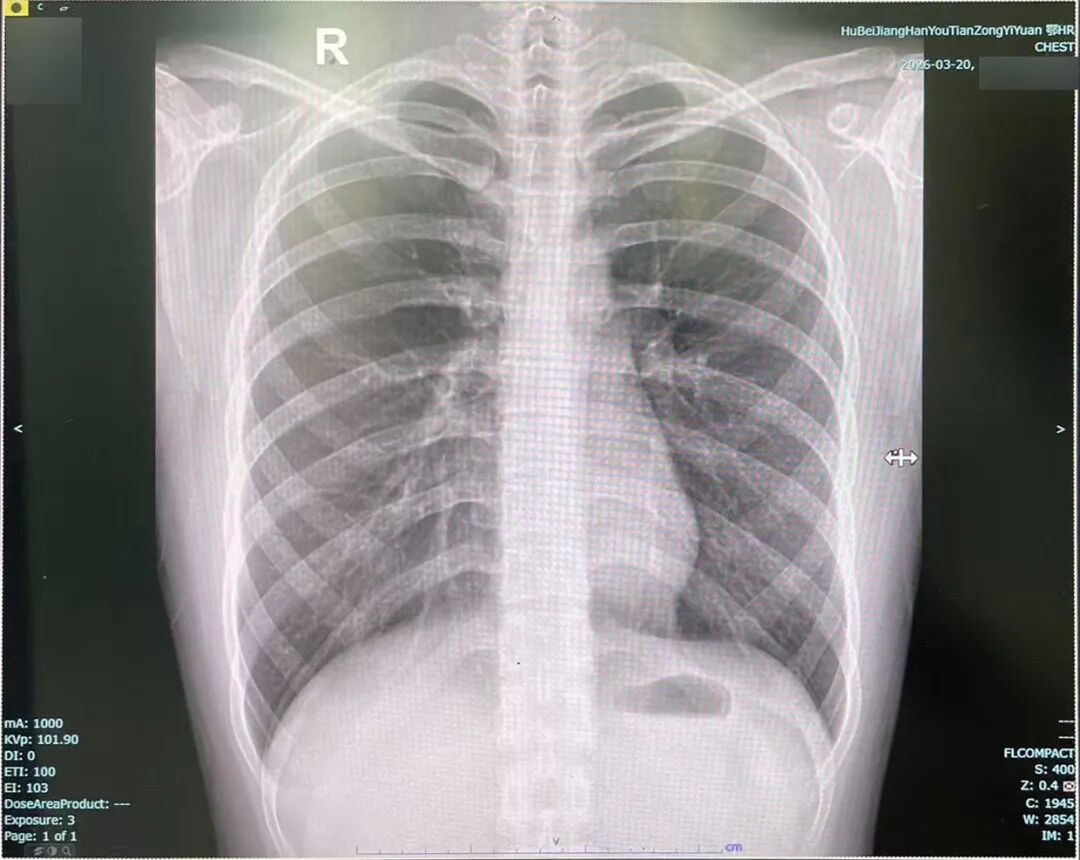

X光片是利用X射线穿透人体,根据不同组织密度不同,来形成有黑白对比的平面图像,常用于检查骨折、肺部炎症等。

我国放射防护标准规定,放射工作人员每年剂量限值是50mSv,而拍一次X光胸片的辐射量大约是0.1mSv,远低于国家规定的安全阈值,因此在规范操作下对人体健康风险极小。

胸部X片(右图)

虽然X光单次检查辐射剂量极低,常规一次胸片、四肢X线检查,对人体几乎无伤害,但仍然建议孕妇(尤其孕早期)、婴幼儿避免非必要检查。